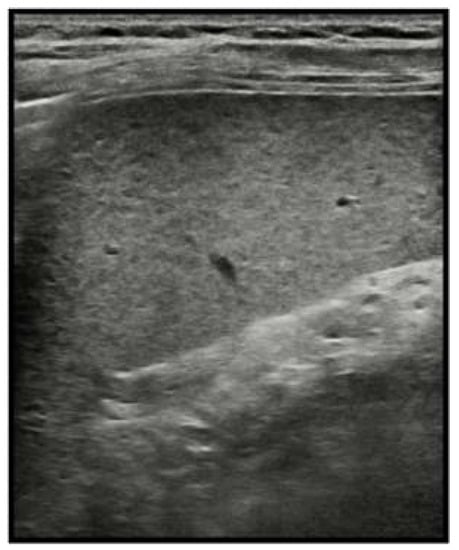

2.6. Infarcts